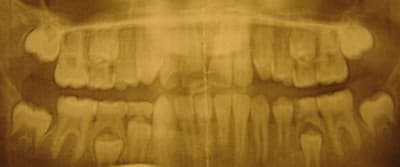

Salut Merci pour vos réponses.. Il s'agit bien de la 75, bien vu (faute de frappe)... Je vous joins la panoramique... J'ai effectivement essayé d'éviter la Spix en commençant par une para-apicale et un complément lingual... douleurs.... donc j'ai fini par sortir la grosse aiguille... Malgré signe de Vincent et tout le tralala, 10/15 minutes d'attente, d'explications et la certitude que le goss était anesthésié, le gosse hurlait... Donc pour la 1ère fois j'ai dû finir malgré la comédie et la mère persuadée que je martirisais son enfant... Pour réagir aux posts plus haut, je comprends que la plupart des dentistes squizzent les gosses... De quoi dégoûter de se casser la tête Il n'en demeure pas moins que cette cellulite m'a surpris... Donc le seul élément particulier de cette extraction c'est peut être l'état de stress du patient... Les boutons sur la lèvre sont effectivement peut être dus à une morsure suite à la Spix... Pour ce qui est de "l'ouverture-drainage" il n'y avait pas d'abcès le jour de l'extrac donc ça n'aurait pas changé grand chose!

nécrose,gangrene pulpaire il y a quand même de quoi provoquer une cellulite avec une AL ? non?surtout sur une racine de dent de lait qui est un espace moins hermétique qu'une dent d"adulte? il n'y a qu'a regarder la radio ou le plancher a l'air atteint,et probable communication!